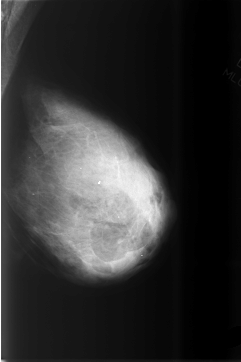

ics_version 1.0 filename C-0505-1 DATE_OF_STUDY 22 12 1998 PATIENT_AGE 57 FILM FILM_TYPE REGULAR DENSITY 4 DATE_DIGITIZED 25 2 1999 DIGITIZER LUMISYS LASER SEQUENCE LEFT_CC LINES 5728 PIXELS_PER_LINE 3872 BITS_PER_PIXEL 12 RESOLUTION 50 NON_OVERLAY LEFT_MLO LINES 5784 PIXELS_PER_LINE 3856 BITS_PER_PIXEL 12 RESOLUTION 50 NON_OVERLAY RIGHT_CC LINES 5800 PIXELS_PER_LINE 3936 BITS_PER_PIXEL 12 RESOLUTION 50 OVERLAY RIGHT_MLO LINES 5872 PIXELS_PER_LINE 3704 BITS_PER_PIXEL 12 RESOLUTION 50 OVERLAY |

FILE: C_0505_1.RIGHT_CC.OVERLAY TOTAL_ABNORMALITIES 1 ABNORMALITY 1 LESION_TYPE CALCIFICATION TYPE DYSTROPHIC DISTRIBUTION CLUSTERED ASSESSMENT 4 SUBTLETY 5 PATHOLOGY BENIGN TOTAL_OUTLINES 1 BOUNDARY |